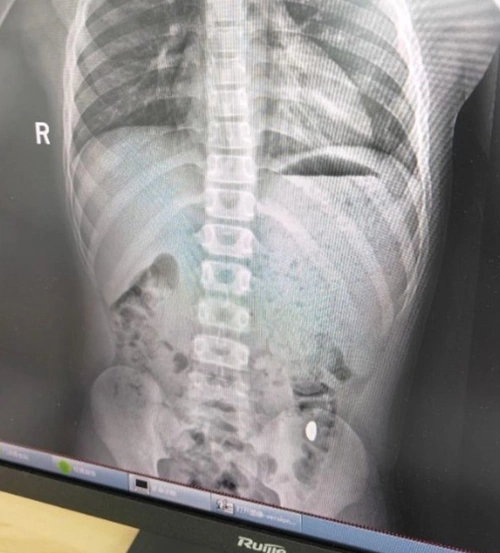

Tuy nhiên, sau 5 ngày liên tục kiểm tra phân của con hai lần mỗi ngày, cô vẫn không thể tìm thấy vàng. Hôm 26/10, Ji đưa con trai đến Bệnh viện Nhân dân số 5 Côn Sơn để kiểm tra, phát hiện "vật thể lạ trong dạ dày". Cuối ngày hôm đó, hạt đậu vàng được lấy ra thành công. Bác sĩ cảnh báo nếu ở lại quá lâu, dị vật có thể gây tắc ruột và yêu cầu gia đình tiếp tục theo dõi.

Kết quả phim chụp cho thấy hạt đậu vàng trong dạ dày cậu bé 11 tuổi. Ảnh: Baidu